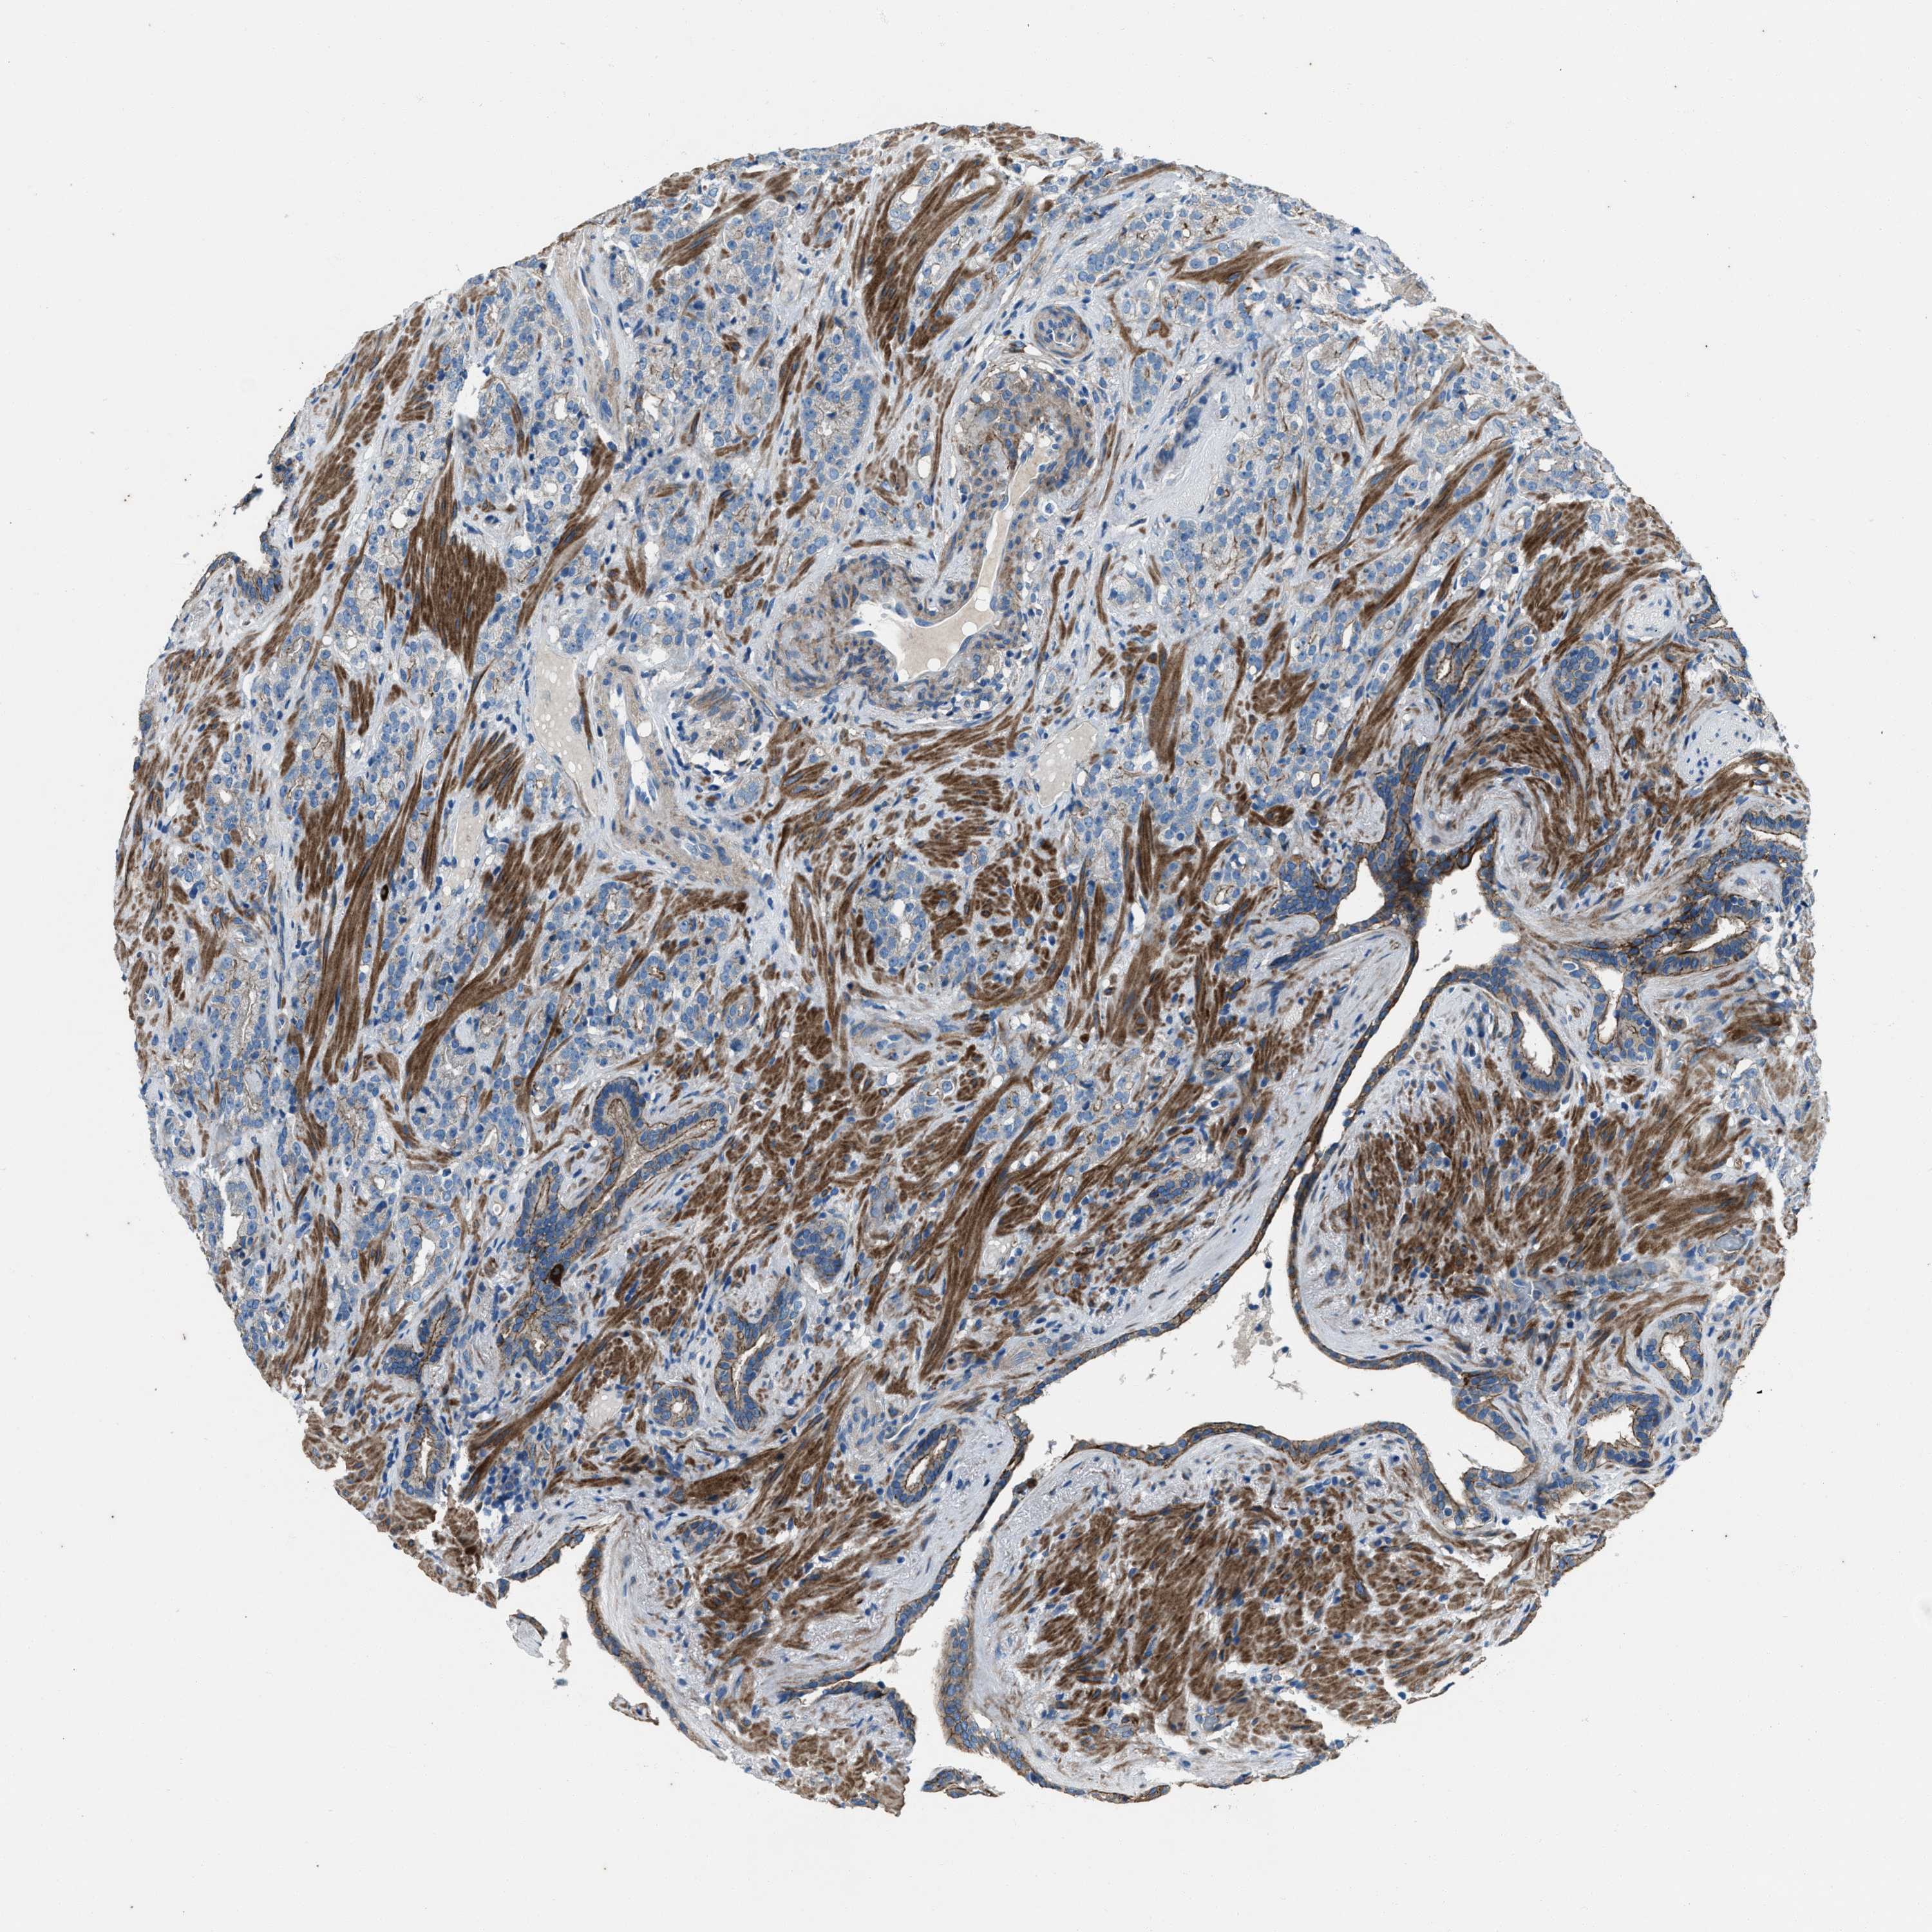

PROSTATE CANCER - Protein expressioni

A mouse-over function shows sample information and annotation data. Click on an image to view it in a full screen mode. Samples can be filtered based on level of antibody staining by selecting one or several of the following categories: high, medium, low and not detected. The assay and annotation is described here.

Note that samples used for immunohistochemistry by the Human Protein Atlas do not correspond to samples in the TCGA dataset.

Antibody stainingi

Antibody staining in the annotated cell types in the current human tissue is reported as not detected, low, medium, or high, based on conventional immunohistochemistry profiling in selected tissues. This score is based on the combination of the staining intensity and fraction of stained cells.

Each image is clickable and will lead to virtual microscopy that enables deeper exploration of all samples and also displays staining intensity scores, fraction scores and subcellular localization as well as patient and tissue information for each sample.

Antibody HPA020095

Antibody HPA020138

Antibody CAB010878

Antibody CAB080402

Staining

High

Medium

Low

Not detected

Intensity

Strong

Moderate

Weak

Negative

Quantity

>75%

75%-25%

<25%

None

Location

Nuclear

Cytoplasmic/membranous

Cytoplasmic/membranous,nuclear

Adenocarcinoma, High grade

Adenocarcinoma, Low grade

Adenocarcinoma, NOS

Adenocarcinoma, Medium grade